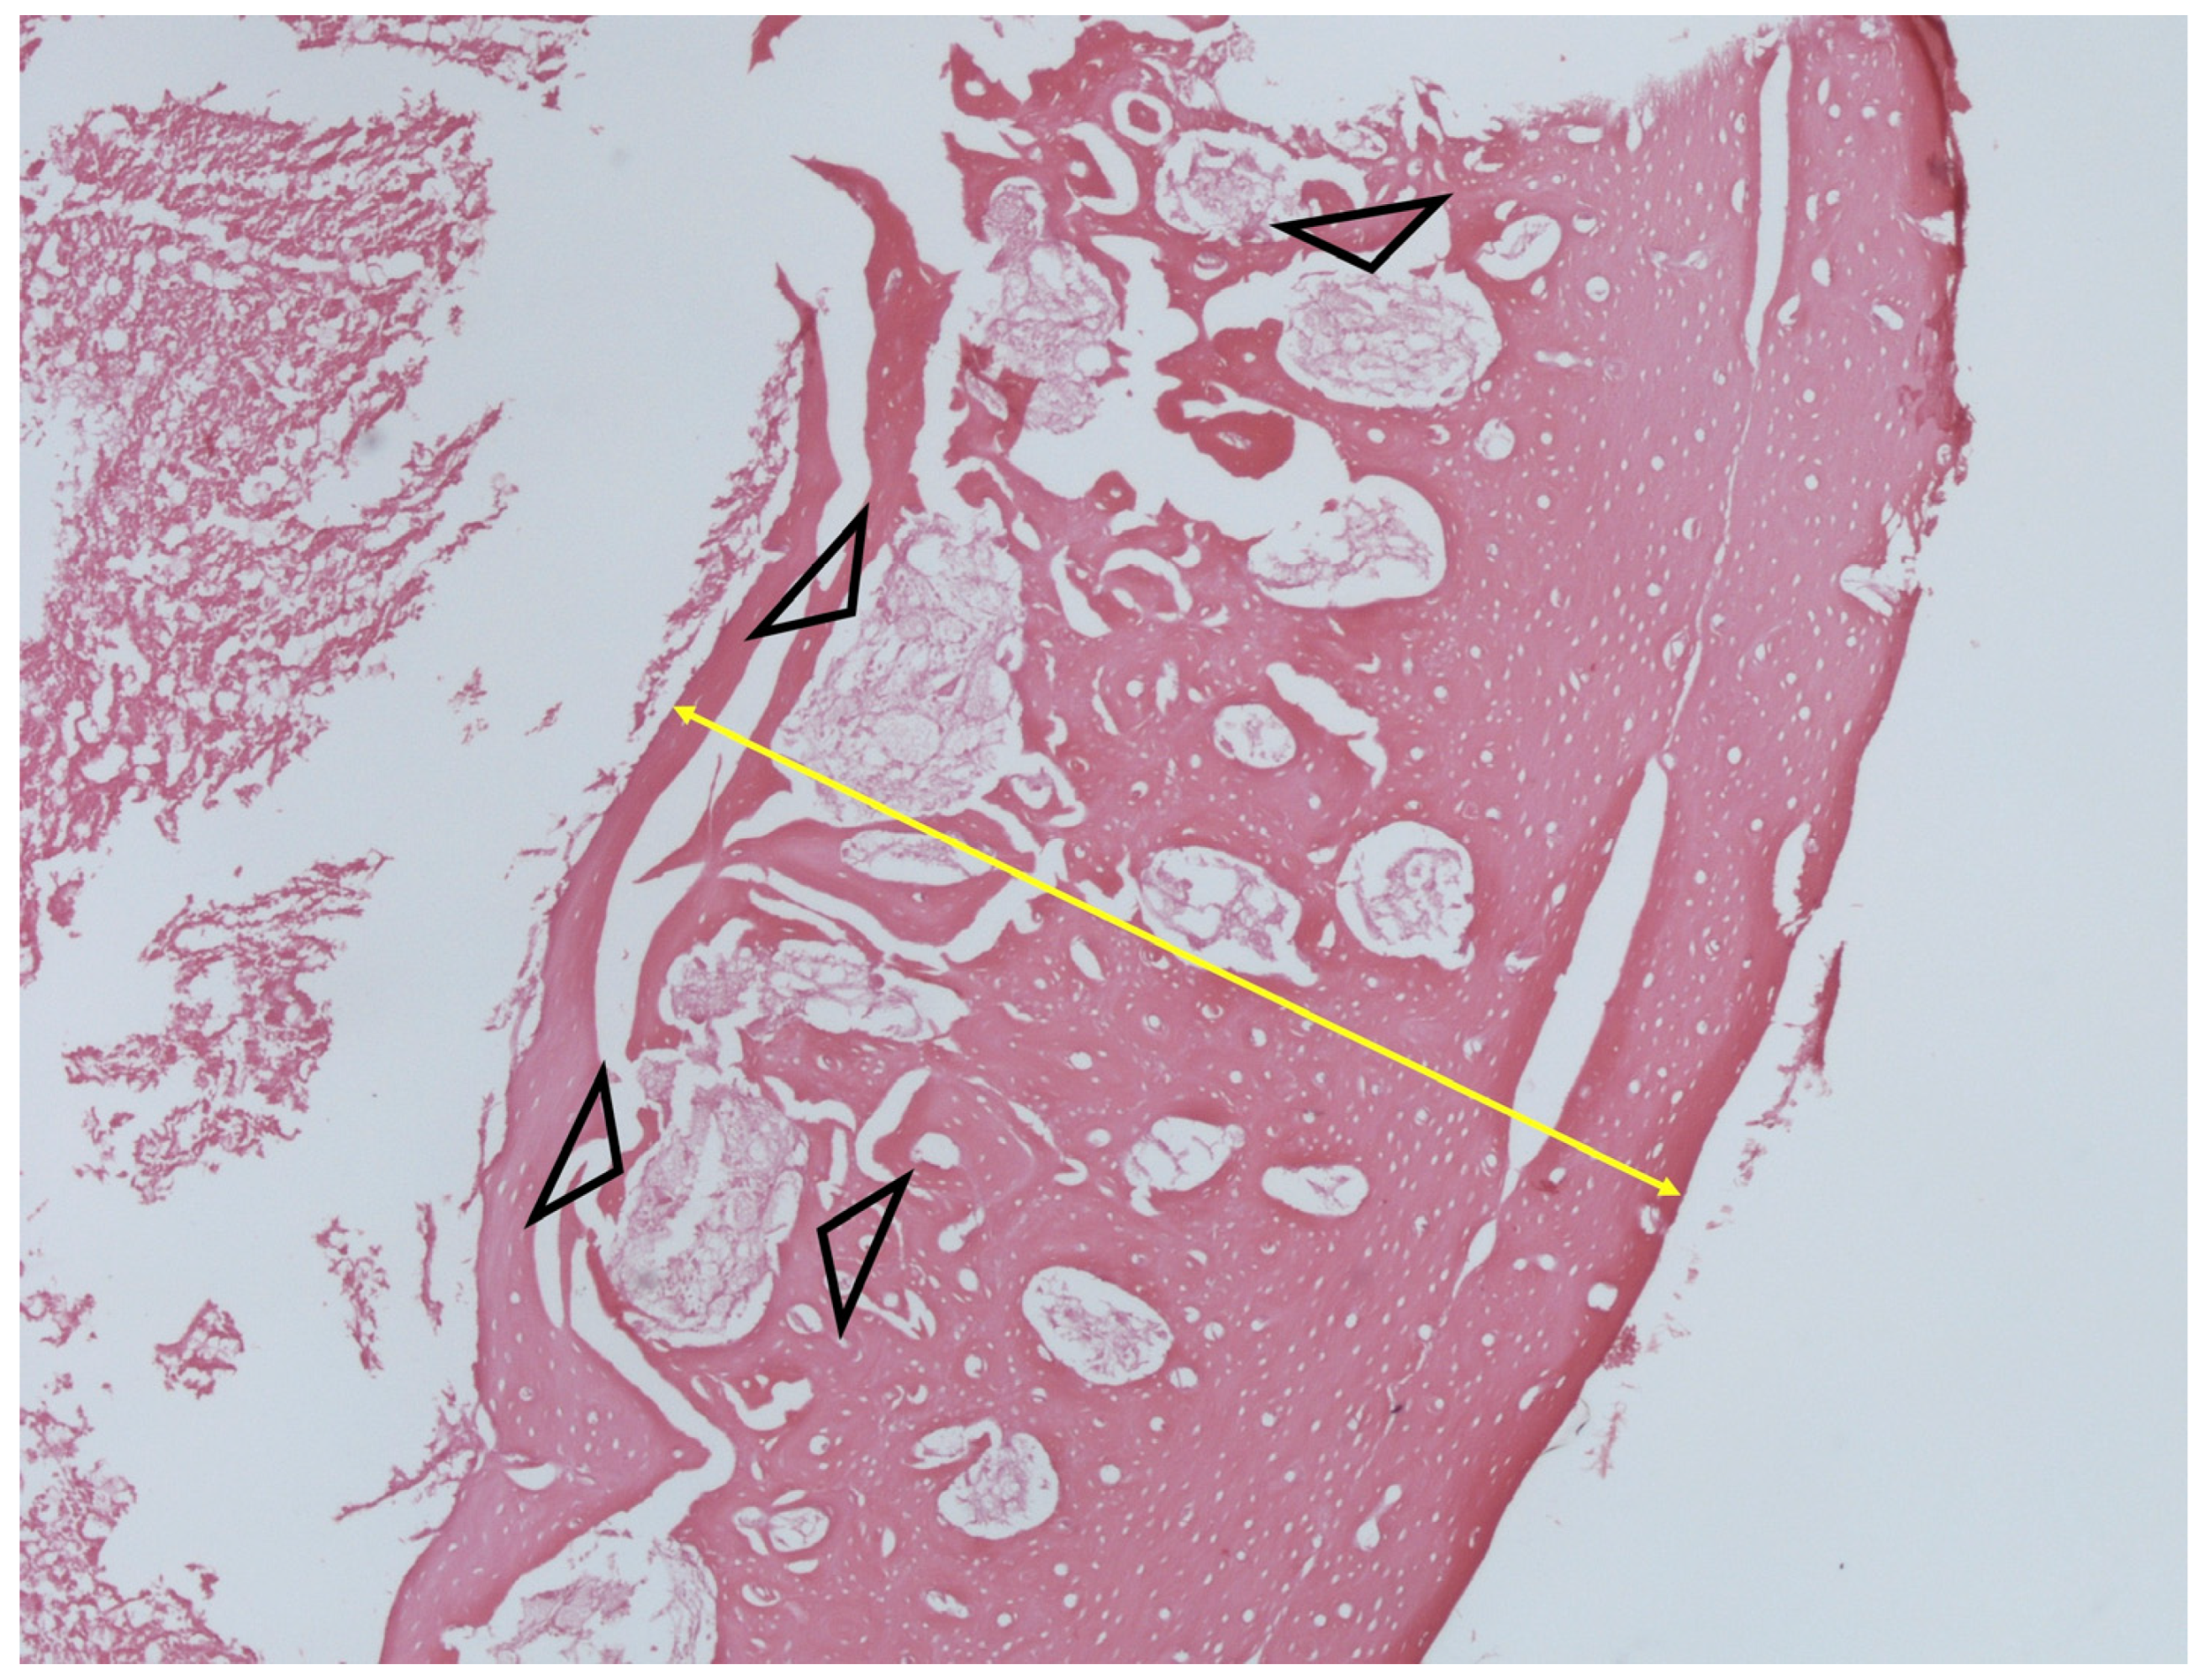

3.5. Histology

Histologic examination of samples from animals without any wound reaction did not reveal any bone or soft tissue abnormality (Figure 5). On the contrary, and in case of infection, loss of normal bone architecture, cortical thickening, and endocortical fibrosis were evident (Figure 6). When foreign-body reaction was apparent, numerous polymeric particles birefringent under polarized light were surrounded by macrophages and giant cells. Disruption of normal architecture with cortical thickening and dysplastic bone marrow were also observed (Figure 7).

Figure 6.

Histological image showing severe cortical thickening (yellow arrow) with diffuse endocortical fibrosis (arrow heads) in an infected bone (H + E stain, ×200).